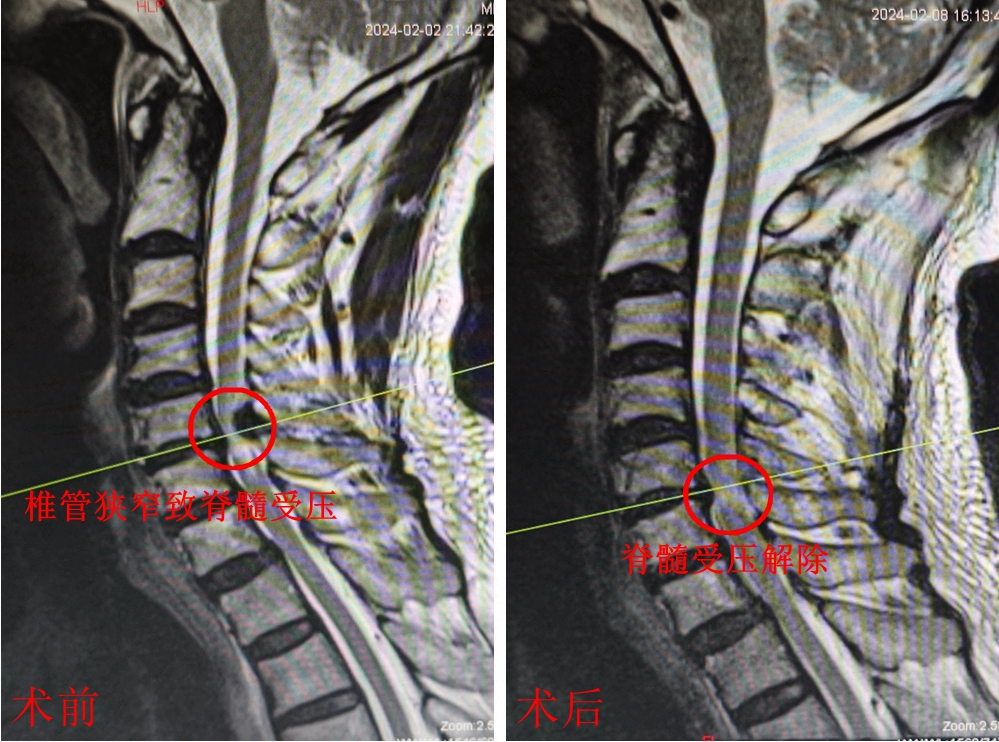

核磁共振显示,术后颈椎脊髓受压解除

蒋某3个月前无明显诱因出现颈部不适,伴有四肢麻木乏力、胸部束带感、行走踩棉花感,在家人的搀扶下来到常德一医就诊。检查发现,蒋某颈椎第5-6节之间的椎管严重狭窄。

常德一医骨科副主任医师、博士董兴成介绍,蒋某的椎管狭窄是由于黄韧带病变引起。黄韧带是相邻椎弓根之间的韧带,位于椎管内,主要由黄色弹性纤维构成,具有维持椎管形态的作用。黄韧带增生、肥厚、钙化,可导致椎管占位,从而对椎管内的脊髓神经造成压迫。脊髓型颈椎病需尽快手术,否则可能导致永久性四肢瘫痪。

2月5日,董兴成医生为蒋某实施了单侧双通道内镜下黄韧带钙化物切除+椎管减压术。